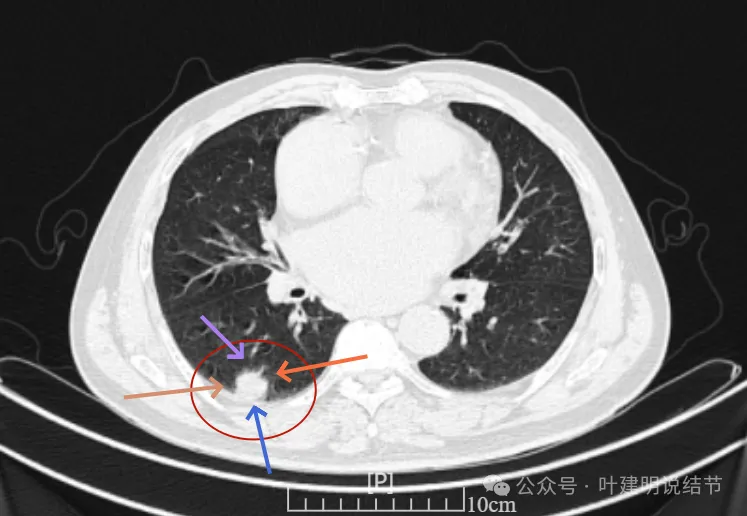

再看2024年6月时的影像:

右下新增病灶,混合密度,整体轮廓较清,瘤肺边界欠清。

有小血管进入,边缘毛糙。

局部有毛刺,但不够锐利;病灶感觉有一层晕似的,邻近胸膜下也有淡磨玻璃影。

实性密度为主,周围少许很淡的磨玻璃影。

边缘不平有毛刺,但不锐利;贴着胸膜但无明显牵拉。局部表面有浅分叶似的,但总体膨胀感不够。

病灶表面不光滑,边上有晕,邻近有淡磨,贴着胸膜无牵拉。

病灶边缘欠清晰,瘤肺边界稍模糊。较宽的基底贴着胸膜。

病灶有血管进入,有浅分叶,实性为主,邻近胸膜有片状淡磨玻璃影,近胸膜无牵拉。但有一定膨胀性。

病灶实性,与血管关系较为密切。

血管走向病灶,但似乎没有被病灶影响,有向内侧的分支甚至没有哪怕一点凹向病灶侧。整体显得偏模糊。

边缘区域杂乱,边糊。